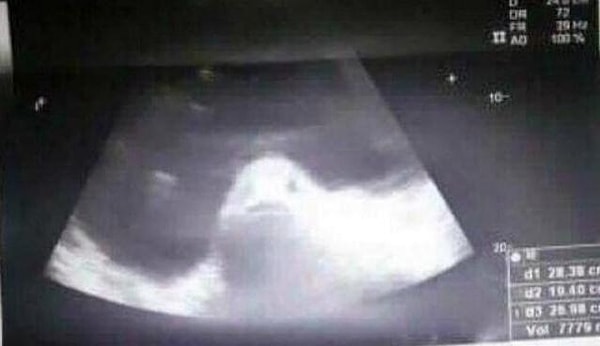

Самое интересное, что на снимке УЗИ действительно можно разглядеть симпатичную губастую рыбешку :D

Впрочем, рыбешкой оказалась самая обычная киста яичника.